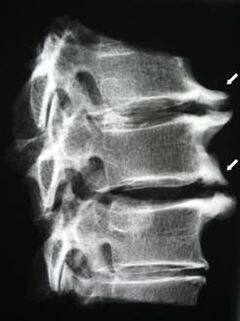

На початкових стадіях остеохондроз виявляється за допомогою МРТ. Пізніше патологію можна діагностувати за допомогою рентгенографії. На рентгенограмах шийного відділу хребта помітні зменшення відстані між хребцями, патологічні зміни фасеткових суглобів, остеофітії.